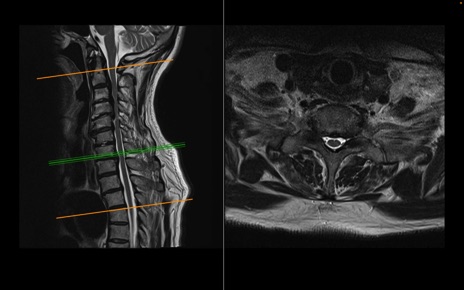

頚椎MRI

T2WI(横断像)

T2WI(矢状断像)